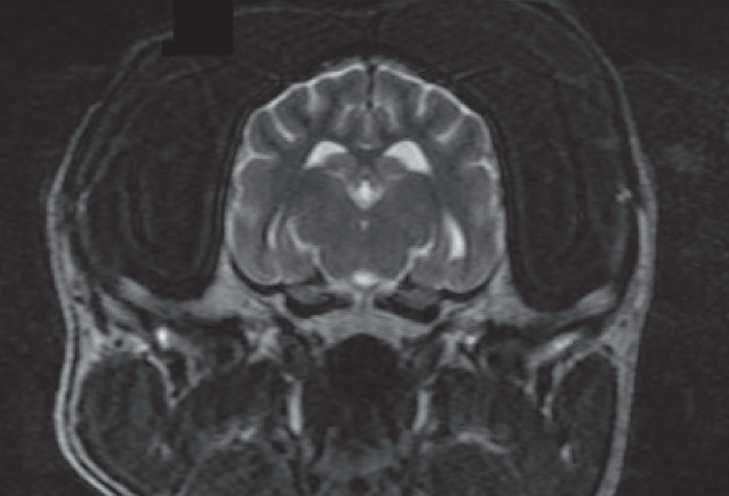

Alrealizarexamenfísicogeneral,noes evidenteningunaanormalidad.Portalmo-

tivo, en un intento de diferenciar vómito de regurgitación, se realiza estudio radiográficosimple(sincambiosradiográficos aparentes) (Figuras 1 y 2) yconmediode contraste (sulfato de bario) (Figura 3); se encuentra un tránsito normal del esófago y del estómago.

Uso del tensor de difusión como una herramienta de diagnóstico en las enfermedades del sistema nervioso central en perros. Reporte de un caso en un husky siberiano con alteraciones del comportamiento.

Use of the diffusion tensor as a diagnostic tool in diseases of the central nervous system in dogs. Report of a case in a Siberian husky with behavioral alterations. .